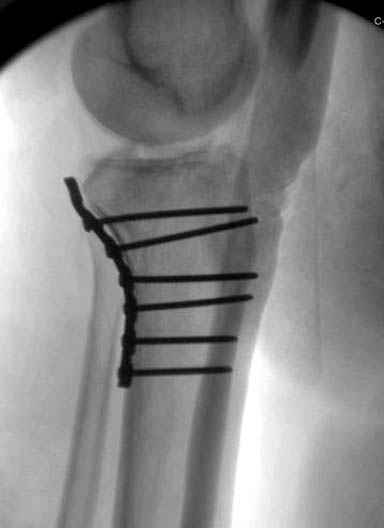

Трудно поверить, что разрекламированная Ортопедическая школа Восточной Украины позволяет такие странные снимки? На прямом снимке сохранен общий контур плато, но не известна судьба импрессии суставной поверхности. На полубоковой?, оставлен без репозиции задне-медиальный отдел, и навряд ли после такой фиксации можно удовлетвориться результатом.

Такая ситуация характерна для многих, когда принимается ошибочное решение, т.е пытаются фиксировать одним имплантом переломы двух мыщелков. Латеральная пластина приемлема только для тех случаев, когда сохраняется интактным медиальный диафизарный кортекс и отсутствует фрагментация на верхушке медиального перелома.

Здесь как раз тот случай, когда результат зависит не только от мастерства хирурга, но и от наличия современных методов исследования. Например, КТ которая поможет рассчитать направления шурупов и установку импланта. Кроме этого, поможет определиться с доступом.

На представленных предоперационных срезах КТ огромный задне-медиальный фрагмент расположен больше кзади, чем медиально. Для планирования, кроме поперечных срезов, надо ориентироваться на корональные срезы, которые укажут топографию верхушки медиального фрагмента.

Представленные снимки не информативны, нужны отдельные качественные снимки коленного сустава и голени без ротации.

Надеюсь, представленные снимки разных случаев помогут разобраться в тактике, и критика примется без личной обиды.